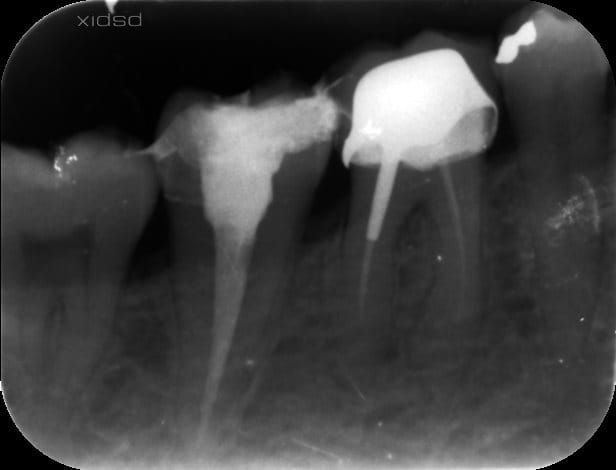

Pulpe vitale

Protaper + localisateur d'apex, Obturation mono cone avec sealite, et IRM par dessus avant de faire l'empreinte pour l'inlay core, c'est ce que je fait tout le temps...

Pas de digue, je sais c'est pas bien, mais déjà avec un rouleau salivaire je me bat avec le patient, alors la digue, bon courage... mais c'est vrai que je vais m'y remettre.

aller t'inquiètes pas , avec un peu de chance , ça peut être occlusal ton histoire .en tout cas ça ne mange pas de pain que d'essayer ce que je te dis .

ça fait même plus style interférence que prématurité . çad lors des mv de latéralité et dû à un sur guidage vestibulaire .si ç est ça la sensibilité est souvent + importante le matin .

donc gros papier bleu que tu fais mordre aussi en latéralité.

tu supprimes tous les contacts vest ,+ les crêtes proximales ,et surtout la distale .et tu repolis ,bien sur .

je vais retoucher en latéralité, si ça persiste, je ferais faire un cone beam pour m'assurer qu'il n'y ait pas de canal non obturé... arfff!